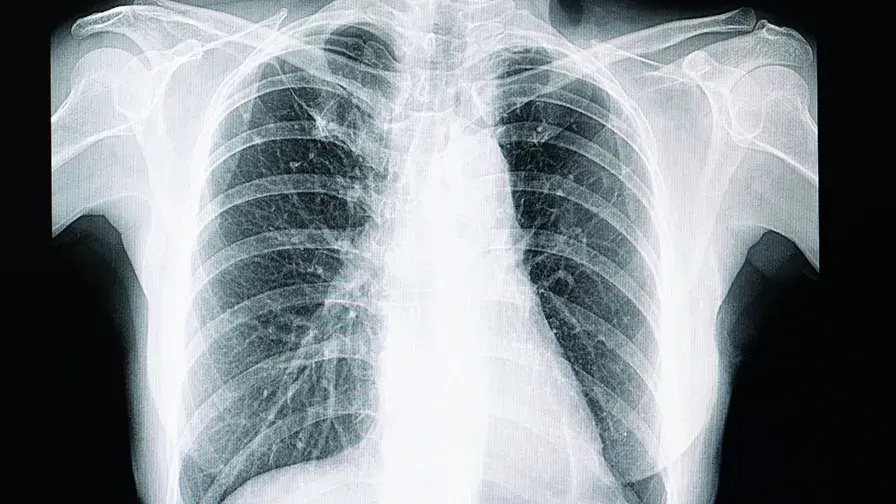

Etude - Effets précoces de l’association elexacaftor-tezacaftor-ivacaftor chez les patients atteints de mucoviscidose et de maladie pulmonaire sévère

Des équipes du service de pneumologie de l’hôpital Cochin AP-HP, de l’Inserm et d’Université de Paris ont étudié les effets précoces de l’initiation de l’association elexacaftor-tezacaftor-ivacaftor (Kaftrio®) chez des patients atteints de mucoviscidose et de maladie pulmonaire sévère. Les résultats de cette étude, coordonnée par le Pr Pierre-Régis Burgel, qui ont fait l’objet d’une publication dans la revue American Journal of Respiratory and Critical Care Medicine le 18 février 2021, indiquent une amélioration rapide de l’état de santé des patients après l’initiation du traitement par elexacaftor-tezacaftor-ivacaftor.

Les essais cliniques de phase 3, qui ont conduit à une autorisation de mise sur le marché européen en août 2020, ont montré que ce traitement entraînait un gain significatif de fonction pulmonaire et de qualité de vie, ainsi qu’une réduction des exacerbations pulmonaires chez les patients éligibles. Ces essais cliniques excluaient les patients ayant une atteinte pulmonaire sévère, du fait d’une crainte de la survenue d’effets secondaires graves et de l’hypothèse d’une moindre efficacité chez ces patients.